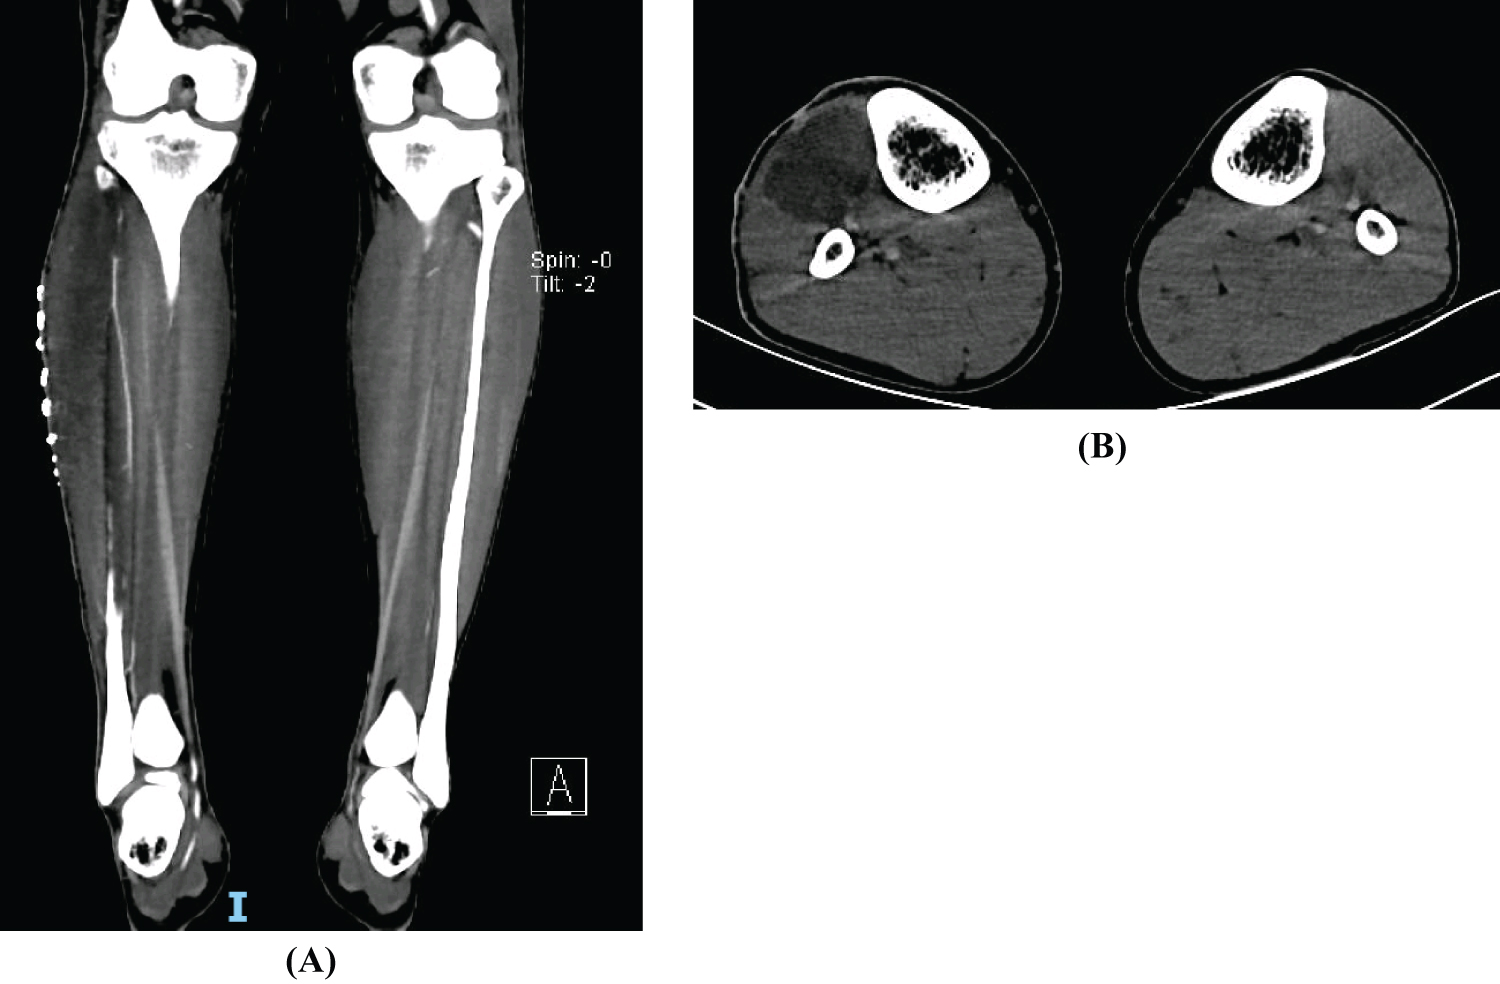

After 10 days the patient returns to the ED with aggravating symptoms. Examination demonstrated tension and pain over the anterior compartment of the leg, hallux hypoesthesia and inability to dorsiflex his right ankle and extend the right hallux and toes. Laboratory findings showed a slight decrease in creatinine kinase (1347 U/l), maintaining slight leucocytosis (11400/μl) and elevation of the hepatic cytolysis pattern (AST 167 U/l and ALT 264 U/l). Leg ultrasonography showed no vascular abnormalities but revealed increase muscle volume (tibialis anterior) with a fibrillar pattern and diffuse hyperechogenicity, associated with slight oedema, reflecting an inflammatory process with a possible hematoma component (Figure 1A and Figure 1B). The patient was diagnosed with an acute anterior compartment syndrome of the right leg associated with rhabdomyolysis and neurological suffering. Right leg pressure measurements revealed an anterior compartment pressure of 80 mmHg whilst lateral and posterior compartments showed normal values. On this basis, an emergent anterolateral right leg fasciotomy was performed (Figure 2). Intra-operative exploration revealed a devitalized tibialis anterior muscle but an intact peroneal nerve. Fasciotomy closure was done 5 days later.

Figure 1: Right Leg ultrasonography (A) An increase muscle volume (tibialis anterior muscle) with a fibrillar pattern and diffuse hyperechogenicity, associated with slight oedema, reflecting an inflammatory process with a possible hematoma component; (B) Image compatible with proximal muscle rupture of 7 mm. View Figure 1